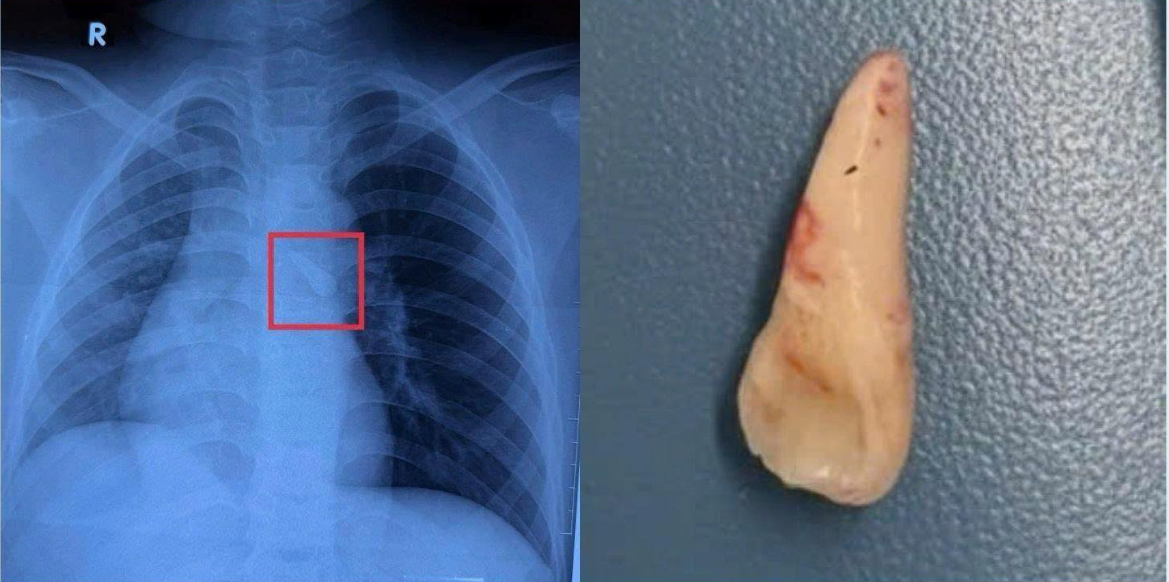

Hình ảnh X-quang của bé ghi nhận một dị vật cản quang ở khí quản. Khai thác bệnh sử và tổn thương vùng hàm mặt thấy bé bị mất răng số 21, từ đó nghĩ đến khả năng răng bị hít sặc vào đường thở sau chấn thương mà bé không để ý.

Hình ảnh X-quang của bé ghi nhận một dị vật cản quang ở khí quản - Ảnh BVCC

Qua nội soi, TS.BS Việt ghi nhận dị vật là một chiếc răng nằm trong carina của khí quản và đã gắp ra thành công. Sau phẫu thuật, đường thở của bệnh nhi thông thoáng, không ghi nhận chảy máu hay biến chứng. Trẻ tỉnh táo, hô hấp ổn định, ăn uống được và tiếp tục được theo dõi tại khoa.